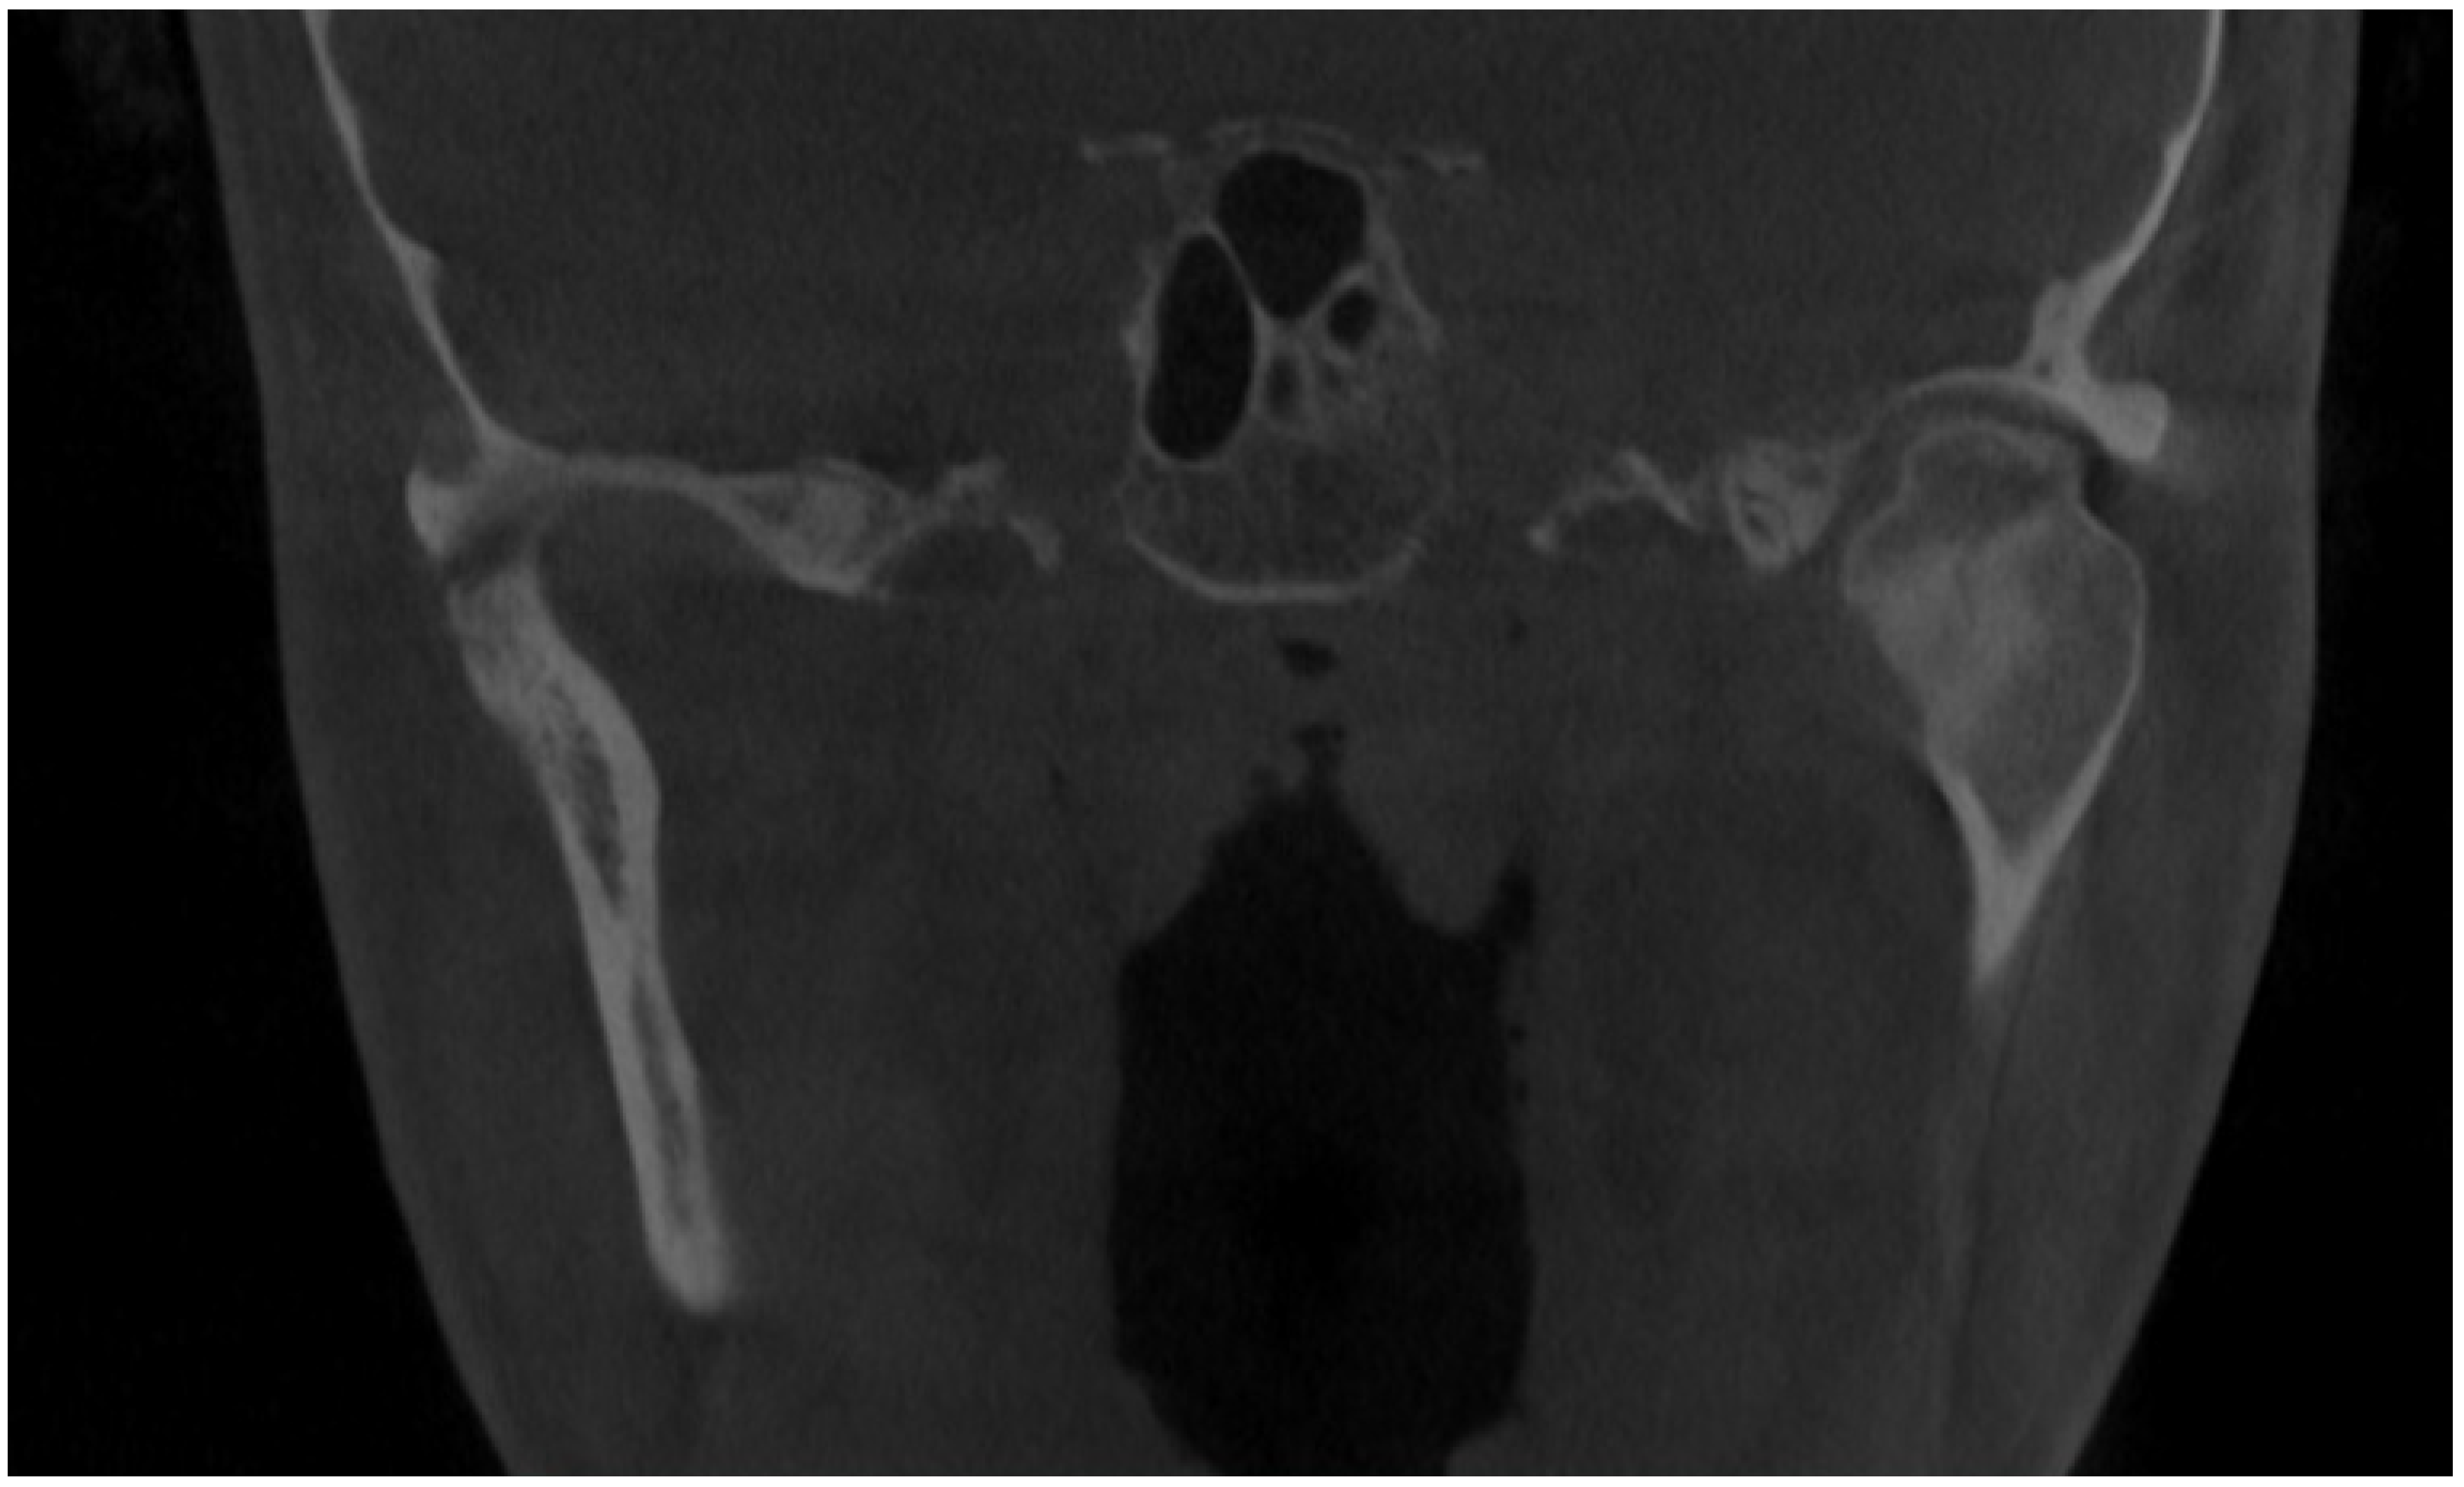

Initial scan—CBCT, coronal view—enlargement and overgrowth of left condylar head causing visible mandibular and skeletal asymmetry. The patient underwent orthodontic treatment (2006–2010) and scheduled BSSO (bilateral sagittal split osteotomy) for surgical correction of the asymmetrical mandibular and featured dentofacial deformity. Six years after the procedure, the patient demonstrated signs of re-occurrence of mandibular asymmetry. After some corrective orthodontic approaches, consultations, and treatment proposals, the patient was scheduled for consultation in our ward (2021–2022). Because of severe mandibular asymmetry, unilateral open bite, chin deviation, midline shift towards the healthy right side, enlargement and overgrowth of the left mandibular basis and ramus, a suspicion of condylar hyperplasia was raised [1,2]. Because the CBCT scans revealed overall extensive progressive growth of the left condylar head, a decision for additional SPECT was decided. According to the known literature, a one-sided open bite with chin deviation towards the heathy opposite side, followed by mandibular corpus enlargement and elongation, are quite common clinical syndromes of condylar hyperplasia. The scope of visible changes in mandibular anatomy is greatly dependent on the time of this abnormal pathological growth and its intensity. It is quite important to evaluate each patient individually because mandibular abnormal growth might not only lead to dentoalveolar changes but also skeletal changes, which, depending on their intensity, might require some degree of surgical intervention. Rarely, condylar hyperplasia might present itself as an osteochondroma or other rare temporomandibular joint tumors [1,2,3]. Therefore, each case of asymmetry, bone change, visible bone enlargement, and overgrowth should be carefully evaluated. Abbreviations: CBCT—cone beam computed tomography, SPECT—single-photon emission computed tomography.